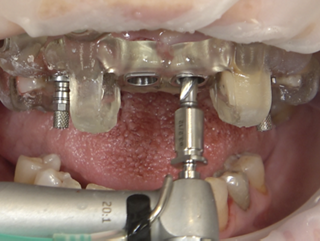

• Guided osteotomy per iGuide® protocol (sequential, depth-controlled).

• Fully guided implant insertion using the iGuide® implant driver with vertical stop.

• Implant drivers left engaged to stabilize the guide; fixation pins drilled precisely.